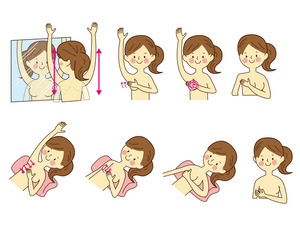

普段からご自分の乳房を見て・触ってみましょう

- 乳房を鏡に映し、両腕を高く上げたり、まっすぐに下ろしたり、両腕を腰にあて、乳房の変化をチェックします。その際、左右の乳房の「ひきつれ」「くぼみ」「ただれ」がないか確認してください。

- 乳房全体とわきの下を指の腹で、乳房全体をゆっくり触ります。特に、乳がんが発生しやすい部位と言われている「乳房の外側上部」に意識を向けてみてください。また、脇の下も触ってみましょう。入浴時に撫で洗いしてみるのも良いでしょう。

- 乳首を軽くつまみ、分泌物がないか調べます。

仰向けに寝た状態や、入浴時に石鹸を付けた手で触ることで「しこり」がわかりやすくなります。